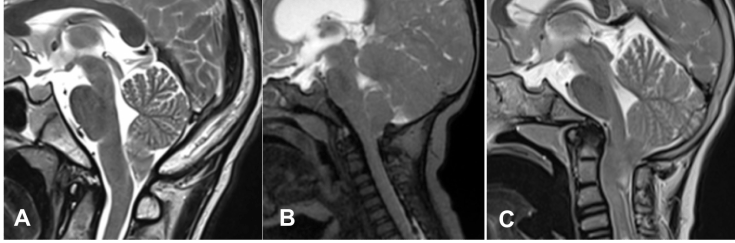

engagement tonsillaire de gravité variable ; le patient A avait une syringomyélie très symptomatique et a été amélioré en postopératoire. il faut considérer que l’imagerie n’est qu’un instantané qui ne reflète pas nécessairement le processus dynamique hydraulique du Chiari.

l’imagerie est parfois en décalage avec la clinique :

- Chiari apparemment compressif alors que l’enfant est rigoureusement asymptomatique

- à l’inverse, imagerie peu impressionnante alors que l’enfant est symptomatique ou qu’il existe une syringomyélie (cf. ci-dessous)